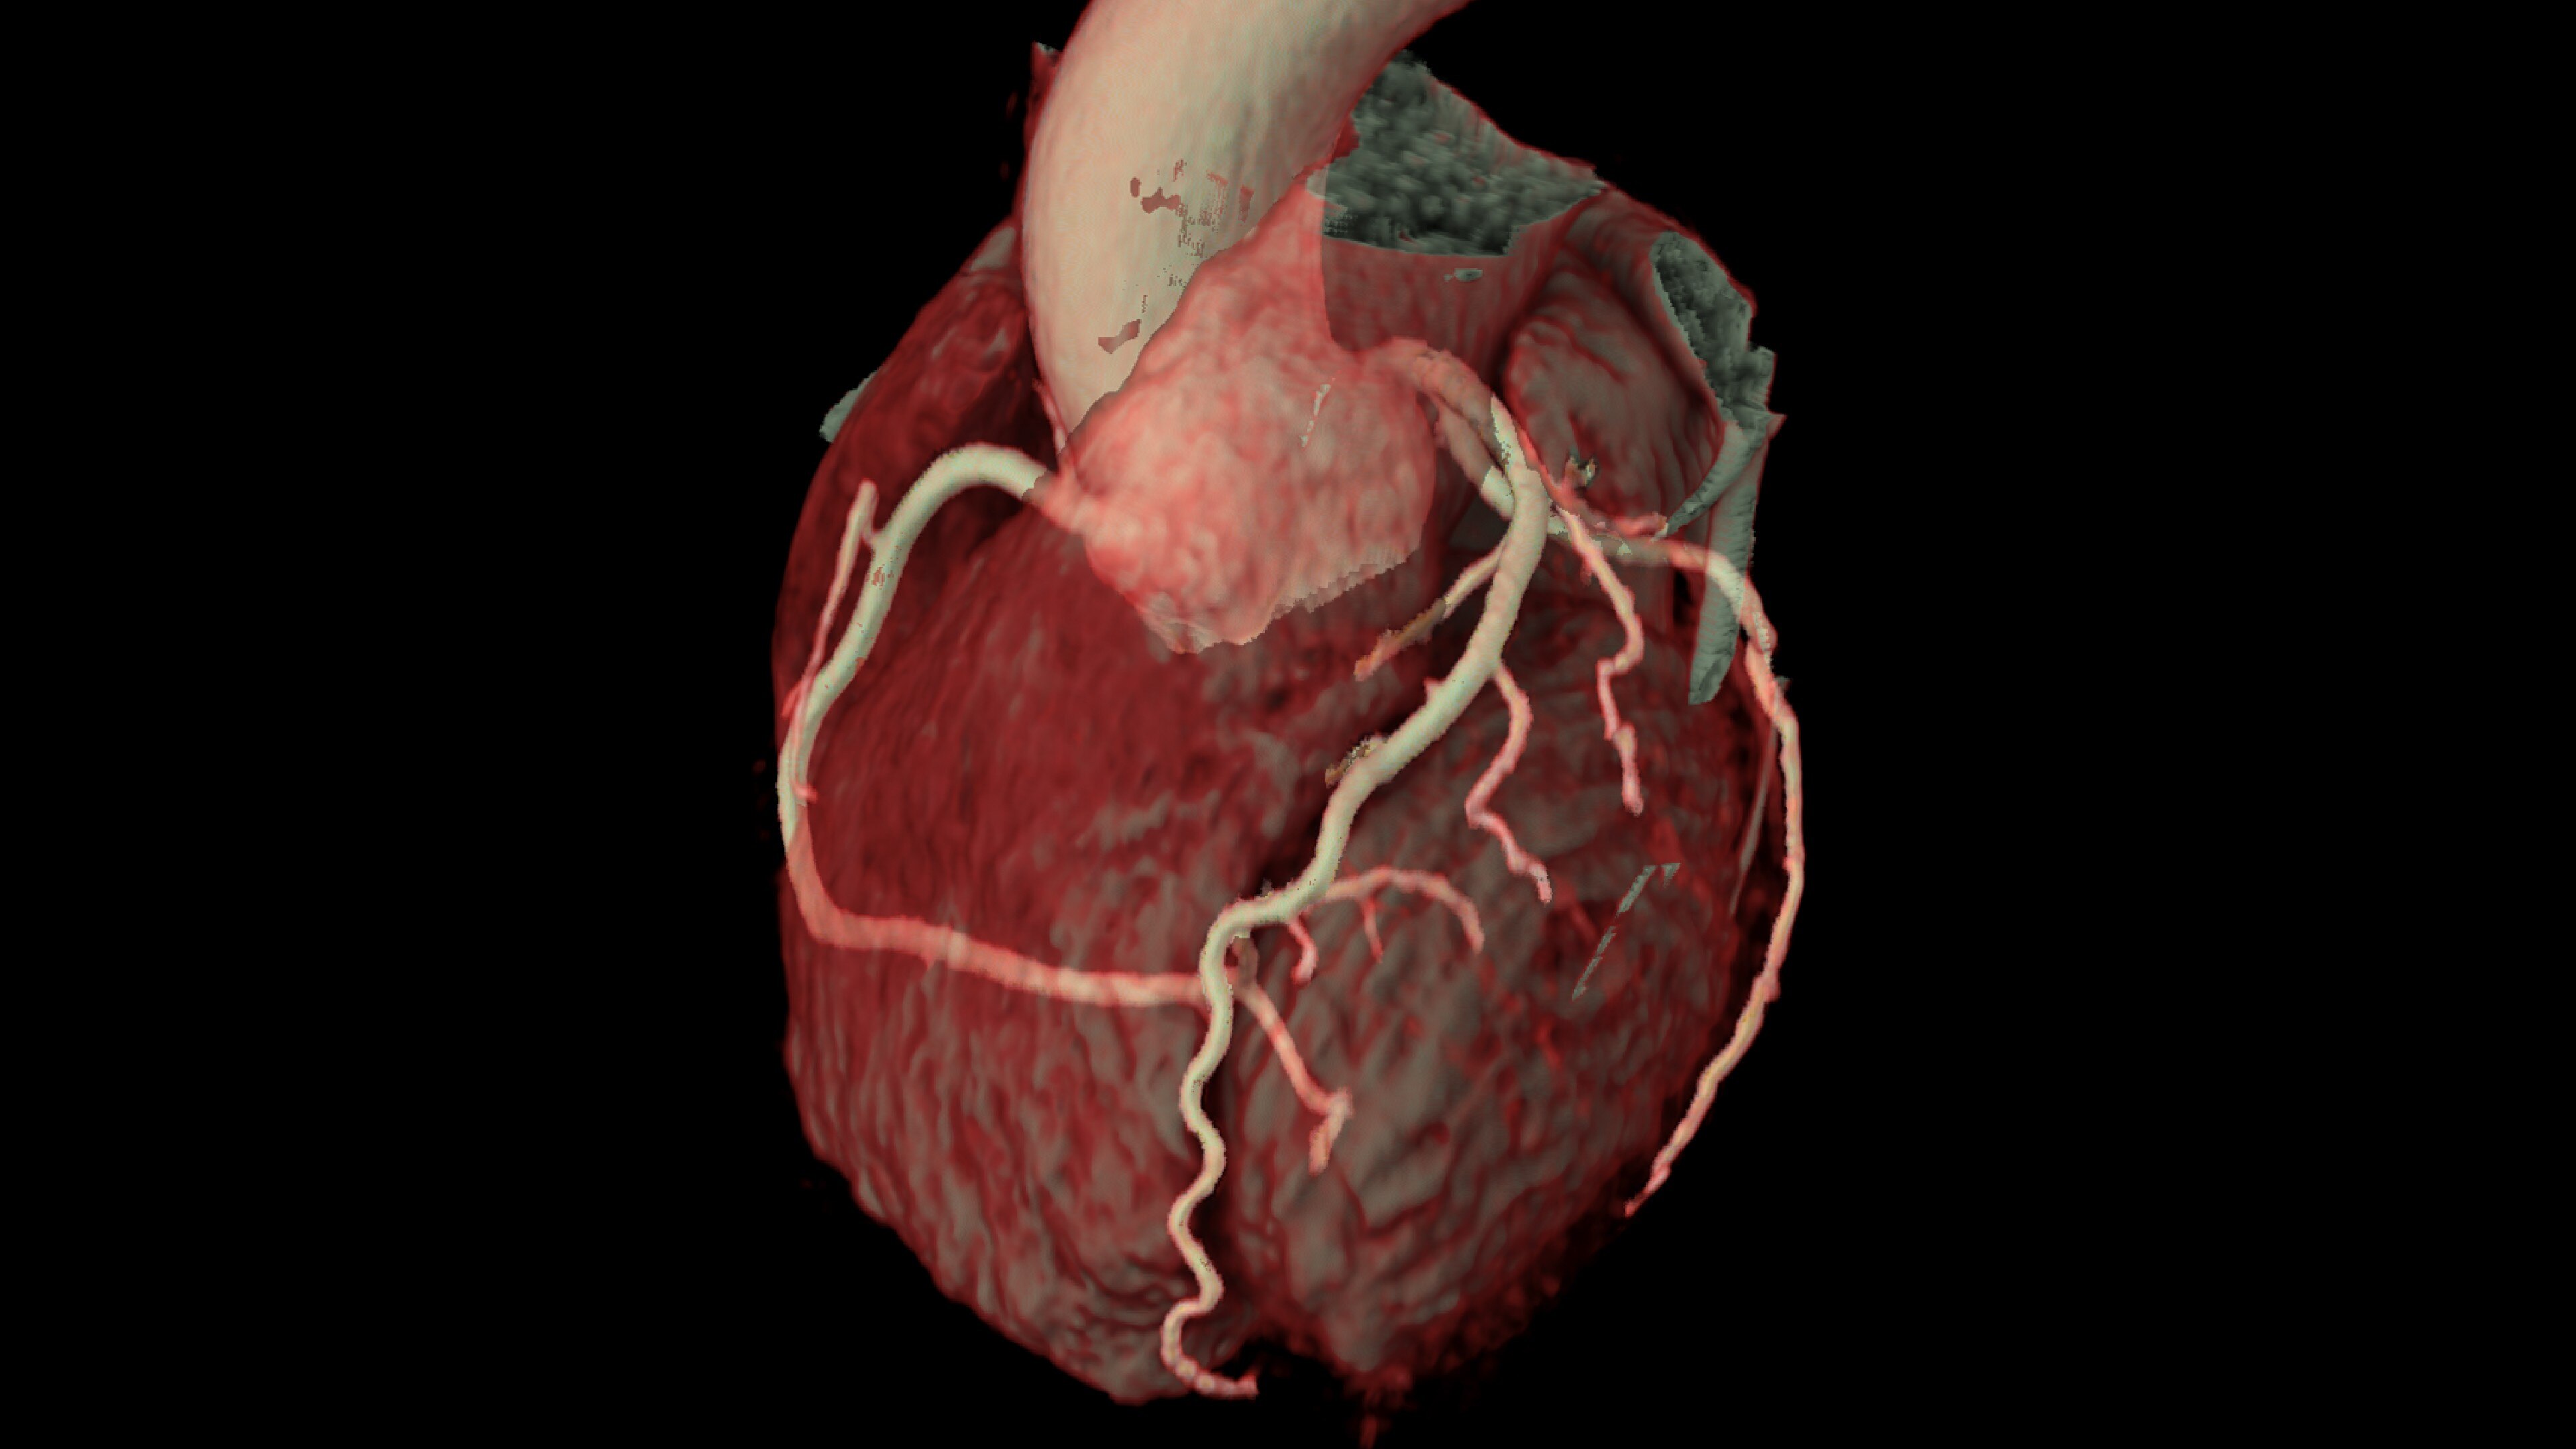

Automatically segments the coronary tree, tracks and labels the coronary arteries

• Auto Coronary analysis automatically segments the coronary tree, tracks and labels the coronary arteries

• Relative perfusion color codes and quantifies percent of hypo-dense areas of myocardium with four selectable color maps and fusion overlays with the coronary tree